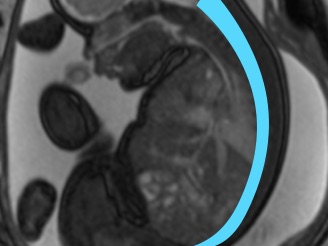

Pelvik ultrason, alt karın bölgesindeki (pelvis) organları değerlendiren güvenli ve radyasyon içermeyen bir görüntüleme yöntemidir. Üç farklı yaklaşımla uygulanabilir:

Transvajinal Ultrason (Vajinadan): Vajinal yoldan yapılan, rahim ve yumurtalıkları daha ayrıntılı gösteren yöntem.

Hastanın mesanesi boşken yapılan bu incelemede, vajinaya ince ve steril kaplı bir prob yerleştirilir. Probun hareketiyle rahim, yumurtalık ve çevresel dokular daha yakından görüntülenir.

Karın üzerinden yapılır.

Özellikle büyük kitlelerde veya transvajinal inceleme yapılamayan durumlarda tercih edilir.

Yağ dokusu fazla olan hastalarda daha net görüntü verir.